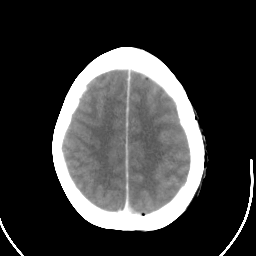

Metastatic bronchogenic carcinoma: Roentgen-ray CT (post-op) -- Slice #17

[Home][Help][Clinical] Slice 17